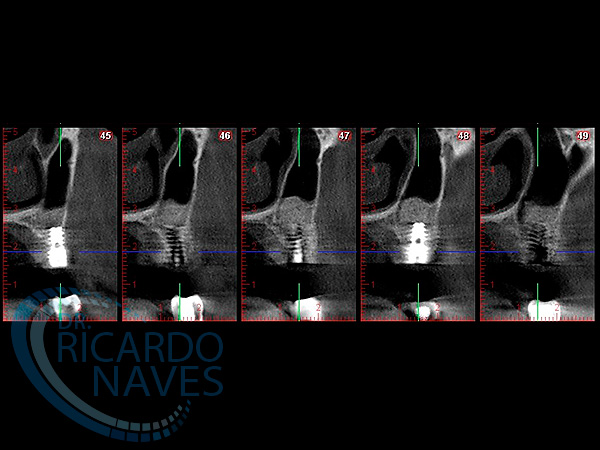

Elevación de seno maxilar con aloinjerto e instalación inmediata de implantes.Control a los 15 días post cirugía.VOLVER Comparte esta historia, elija su plataforma! FacebookXLinkedInPinterestCorreo electrónico